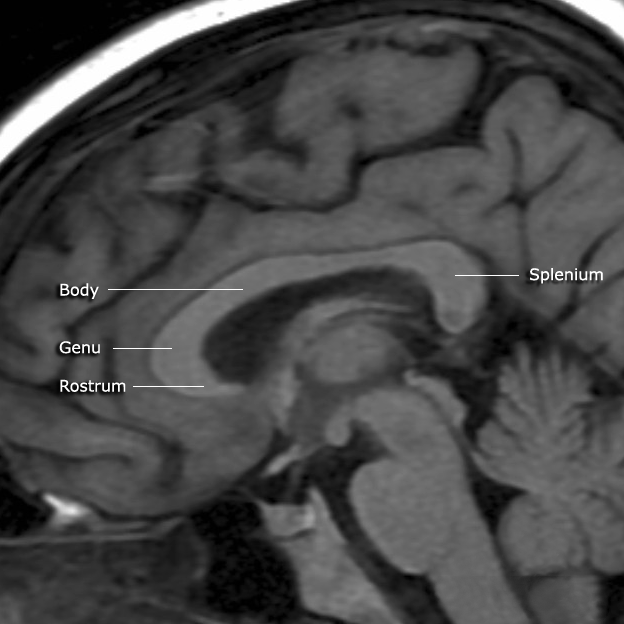

뇌량은 두 개의 대뇌 반구를 연결하는 신경 섬유 다발로, 뇌의 세로 틈새 바닥을 형성한다. 뇌량은 부리, 무릎, 몸통, 팽대부의 네 부분으로 구성되며, 각 부분은 서로 다른 뇌 영역을 연결한다. 뇌량은 좌우 반구의 정보를 통합하여 지각 경험을 형성하고, 양측 운동 협응을 가능하게 하며, 고차 인지 기능을 지원한다. 뇌량의 형태와 크기는 성별에 따라 차이가 있으며, 뇌량 무형성증, 뇌량 절제술, 다발성 경화증, 마르키아파바-비냐미병 등 다양한 질환과 관련이 있다.

뇌량은 크게 부리, 무릎, 몸통, 팽대부의 네 부분으로 구성된다.[4] 앞부분은 전두엽을 향하며 무릎(genu)이라고 불린다. 무릎은 투명 중격 앞에서 아래쪽으로 구부러져 두께가 크게 줄어드는데, 이 얇은 부분은 부리(rostrum)라고 불린다. 부리는 뇌실 사이 구멍에서 시상 기저부의 오목까지 뻗어 있는 종판과 아래쪽에서 연결되어 있다. 뇌량의 뒷부분은 소뇌를 향하며 팽대부(splenium)라고 불린다. 팽대부는 뇌량 중 가장 두꺼운 부분이며, 셋째 뇌실의 맥락총과 중뇌를 덮고 있으며, 두껍고 볼록한 자유 경계로 끝난다. 뇌량의 몸통은 팽대부와 무릎 사이에 위치한다.

뇌량은 네 부분으로 구성되어 있으며, 각 부분은 서로 다른 대뇌 반구를 연결하는 신경 섬유로 이루어져 있다. 뇌량의 앞부분부터 순서대로 부리, 무릎, 몸통, 팽대부라고 부른다.[4]- 부리(rostrum): 뇌량의 가장 앞부분으로, 전두엽의 안와 영역을 연결한다. 부리는 부리와 닮아서 이름이 붙여졌다.

- 무릎(genu): 뇌량의 앞쪽 굽은 부분으로, 전두엽의 전전두피질을 연결하며, 앞쪽으로 굽어 전두엽으로 향하는 섬유 다발인 소집게(anterior forceps)를 형성한다.[4]

- 몸통(body): 팽대부와 무릎 사이에 위치하며, 운동 피질, 감각 피질, 두정엽 등 다양한 영역을 연결한다.

- 팽대부(splenium): 뇌량의 가장 뒷부분으로, 후두엽의 시각 피질을 연결하며, 뒤쪽으로 굽어 후두엽으로 향하는 섬유 다발인 대집게(posterior forceps)를 형성한다.[4] 팽대부는 뇌량 중 가장 두꺼운 부분이며, 셋째 뇌실의 맥락총과 중뇌를 덮고 있고, 두껍고 볼록한 자유 경계로 끝난다. 팽대부는 그리스어로 "붕대"를 의미한다.